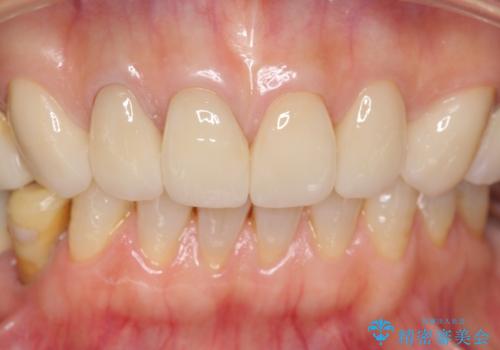

4年半前のクラウン装着時と変わらず、まるで天然歯のように自然に見えました。

患者様の良好なセルフケアと精密な適合の良いクラウンにより、歯肉の腫脹や退縮も認められませんでした。

4年半前に行った治療に大変ご満足頂き、他の部位の治療のため再来院して下さいました。

エコノミーのオールセラミッククラウンに用いられるe-maxはニケイ酸リチウムガラスを主成分にしたセラミックです。

ガラスで出来ていることから非常に透明感があり、審美性と耐久性(強度はジルコニアの方が高い)を兼ね備えた材質です。

(強度 e-max:約400mPa、ジルコニア:900~1200mPa)

クラウンの種類:オールセラミッククラウン エコノミー